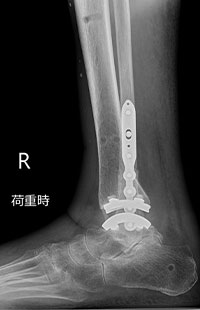

足くびの外側から手術を行う外側侵入型の人工足関節です。

この手術では、まず腓骨を骨切りし、足くびの外側からアプローチします。そこから脛骨と距骨で構成される「距腿関節(きょたいかんせつ)」の表面を削り、人工関節を設置します。特に、距腿関節のみが変形しており、距骨自体のつぶれや他の関節の障害がない方に向いています。人工関節は金属と医療用の特殊な素材でできています。

術前

術後